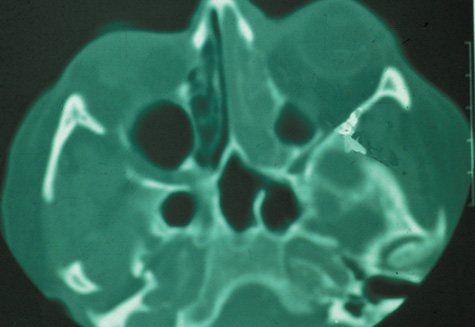

A subperiosteal abscess may rupture or invade the periorbit, resulting in an orbital abscess. This may or may not be contiguous with the subperiosteal collection on CT. There may be gas or air–fluid levels within the mass.51,56,58,59 An orbital abscess may present as an enhancing ringlike peripheral mass that can be either heterogeneous or homogeneous (Fig. 18).

Fig. 18. Orbital abscess. A. Computed tomography of an orbital abscess presenting as an enhancing intraconal mass on right side. B. T1-weighted image. C. T2-weighted image. Note area of high signal corresponding to abscess.